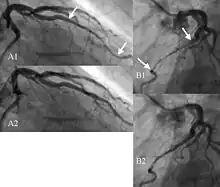

La coronarographie permet d'objectiver l'écrasement systolique de l'artère, cette dernière étant de calibre normal en diastole, mais le trajet intra myocardique n'est pas mis en évidence (pas de visualisation directe du myocarde). La partie proximale de l'artère présente fréquemment des lésions d'athérome[5].